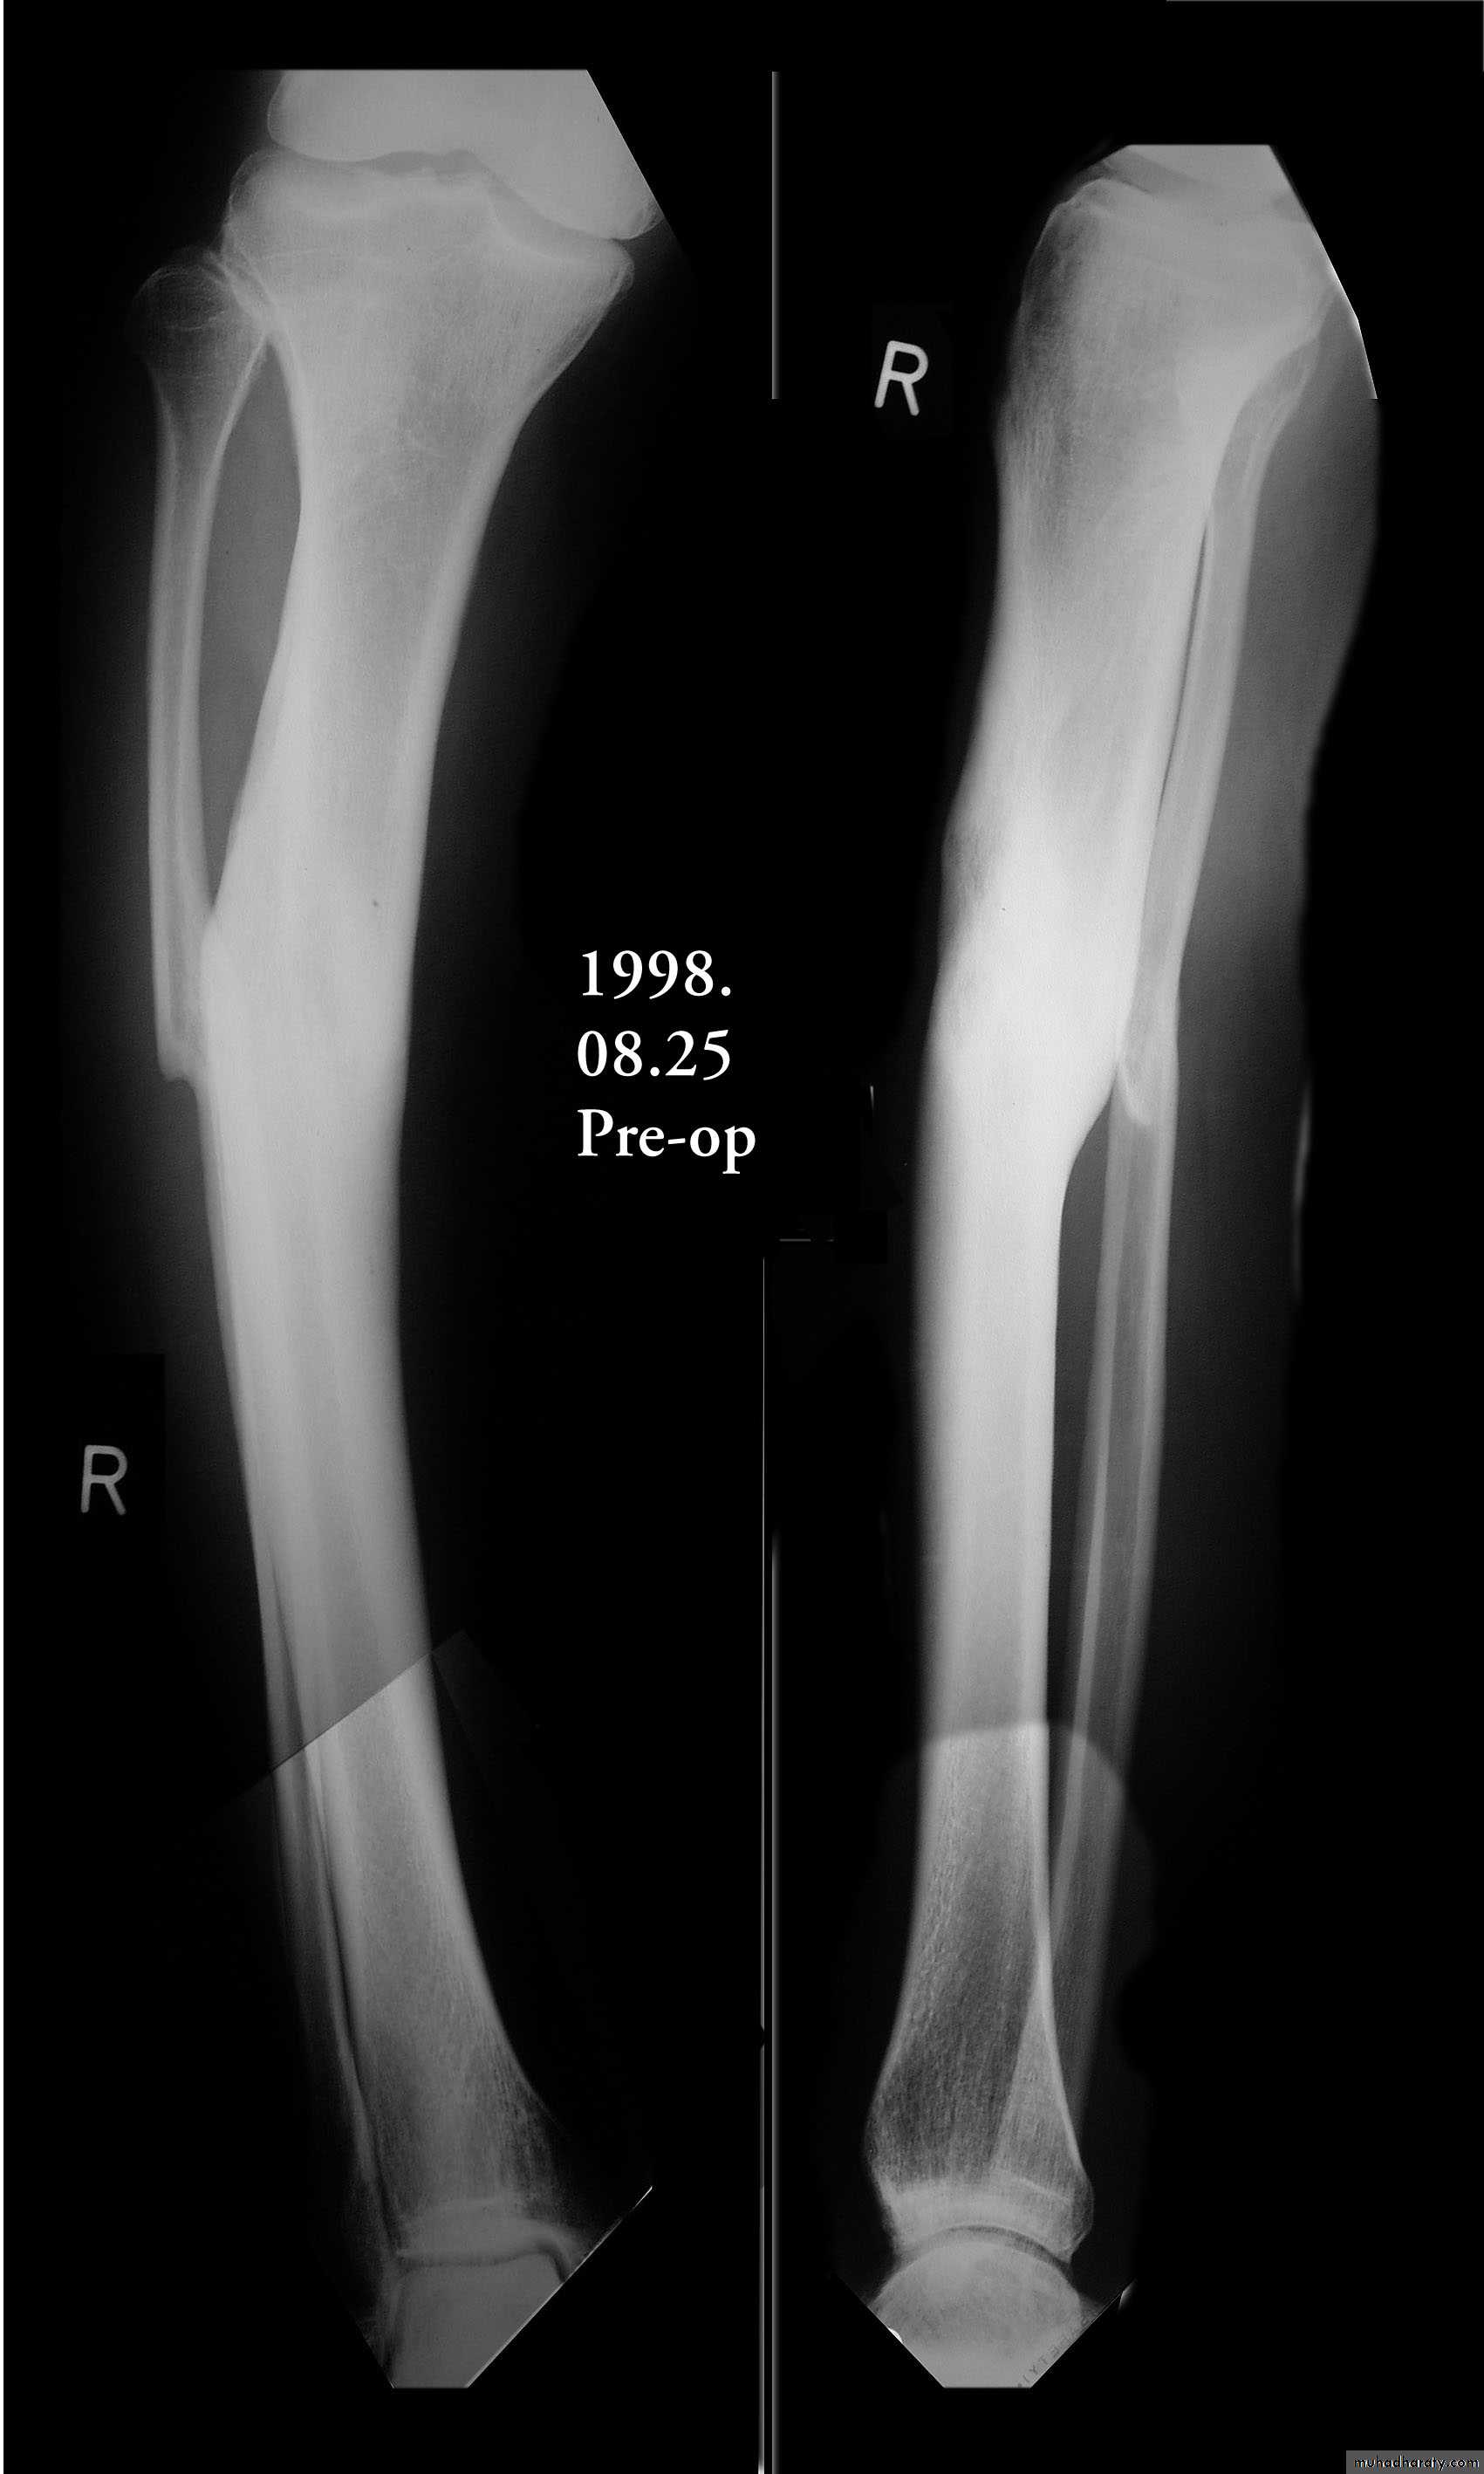

Fractures shaft tibia and fibula

Most fractures in this region involve both the tibia and the fibula. Fractures of the shafts of the tibia and fibula may occur either from an angulatory force or rotational force , Road traffic accident and motorcycle accident are the common cause.Twisting force cause spiral fracture of both bones at different level, while Direct injury crushes the skin and fractures both bone at the same level.

X-ray shows the type and severity of displacement.

Malunited fracture tibia and fibula